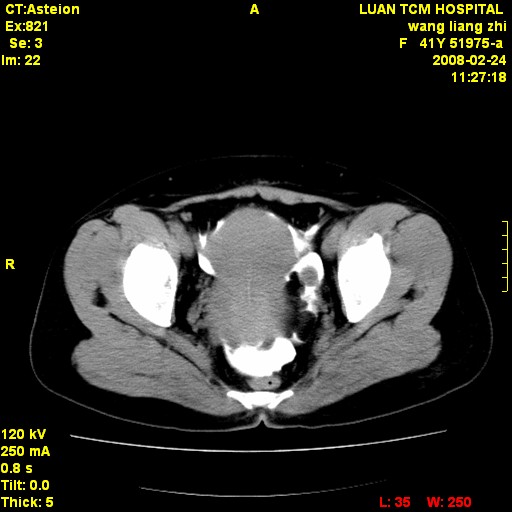

以下是引用dyqct在2009-8-23 16:17:00的发言:[br]考虑:1、造影剂进入腹腔、结肠旁沟、肝周;[br] 2、子宫明显增大(腺肌增生症?);[br] 3、膀胱显影是由于造影剂吸收后经肾分泌进入膀胱的;[br] 4、建议mri检查子宫。